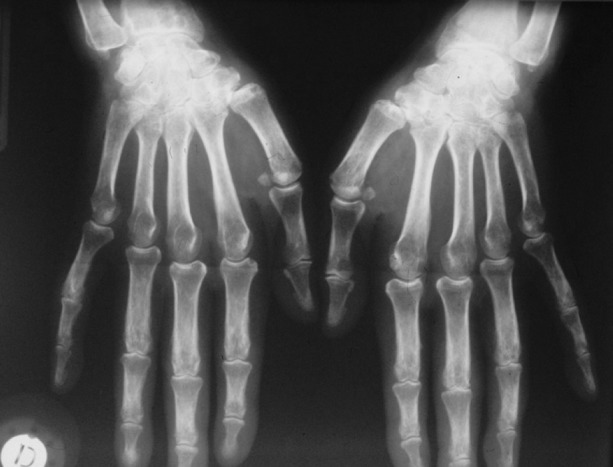

Joint pain or arthritis is the second most common symptom, with synovitis, usually with concomitant fever spikes, occurring in more than two-thirds of patients. All joints can be involved, including sacroiliac and distal interphalangeal joints. In some patients, the presentation is that of a bilateral symmetrical rheumatoid arthritis (RA)-like polyarthritis [3, 7]. Synovial fluid analysis displays high cellularity, >2000 cells/mm3, which confirms joint inflammation. When performed, synovium biopsy reveals only nonspecific synovitis. During the evolution, arthritis becomes erosive in one-third of patients; in these patients, isolated bilateral carpal ankylosis (i.e., without structural damage of metacarpophalangeal or proximal interphalangeal joints, in contrast to RA) is very suggestive of AoSD (Fig. 6.2) [1, 3, 7].

Fig. 6.2.

Ankylosing carpal arthritis in adult-onset Still’s disease